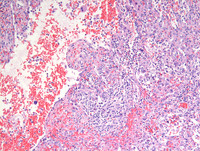

Figure 1: H&E images

Low power photomicrographs reveal a well demarcated tumor within the red pulp and uninvolved spleen at the periphery. Tumor shows proliferation of anastomosing vascular channels interspersed with dilated vascular and cyst like spaces.

Figure 2: H&E images

As noted on medium power photomicrograph (Image on the left), vascular channels have irregular lumina with focal papillary projections. High power photomicrograph (Image on the right) reveals vascular channels that are lined by tall and plump, bland-looking cells, some of which are seen projecting and sloughing into the lumina. Cytologic atypia is not evident.